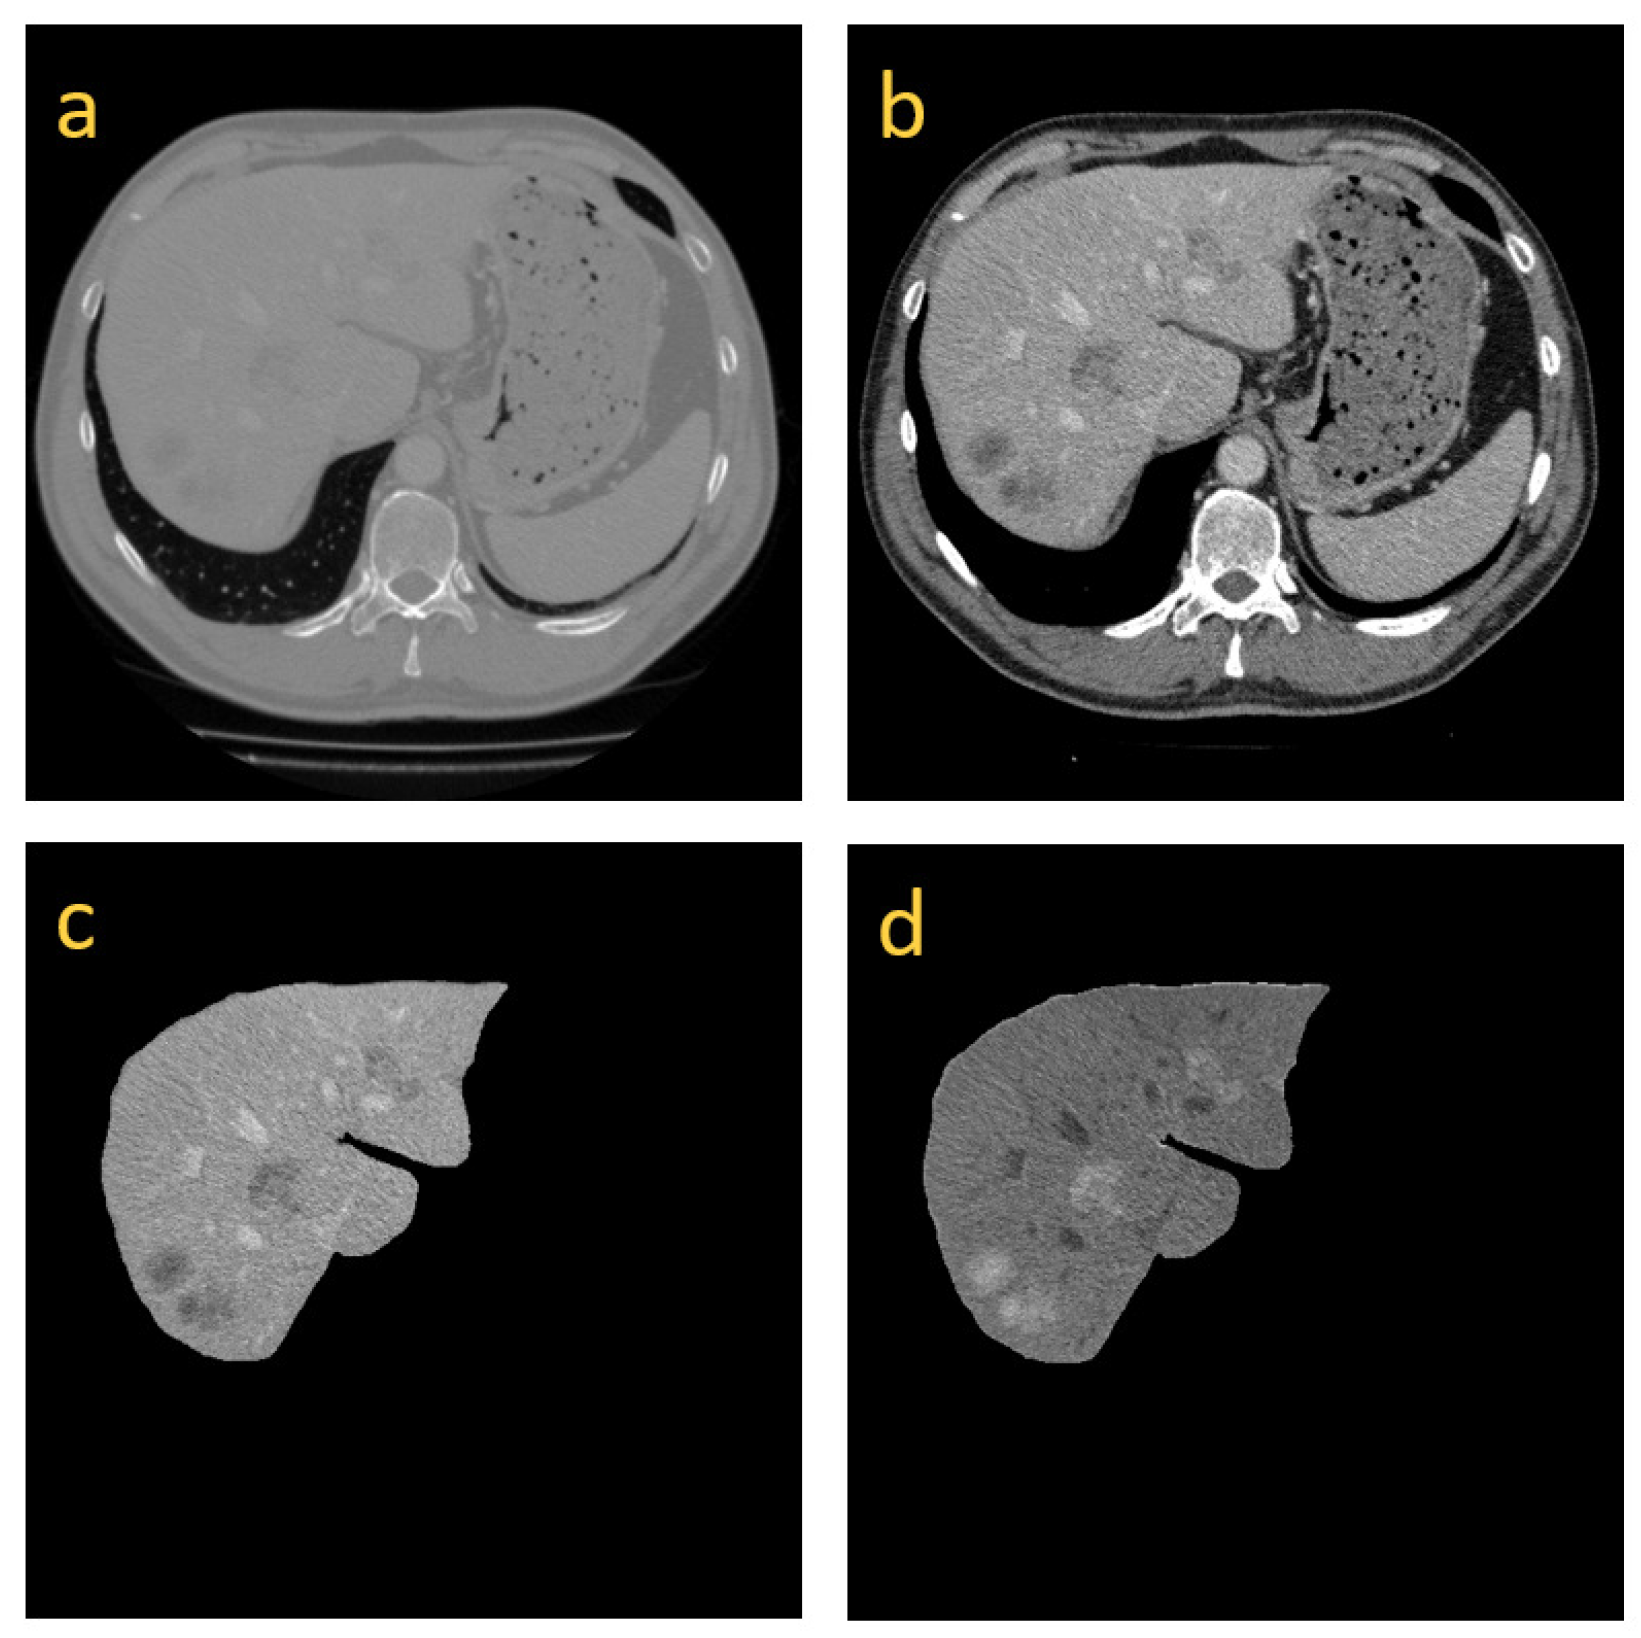

3.1. Image Preprocessing